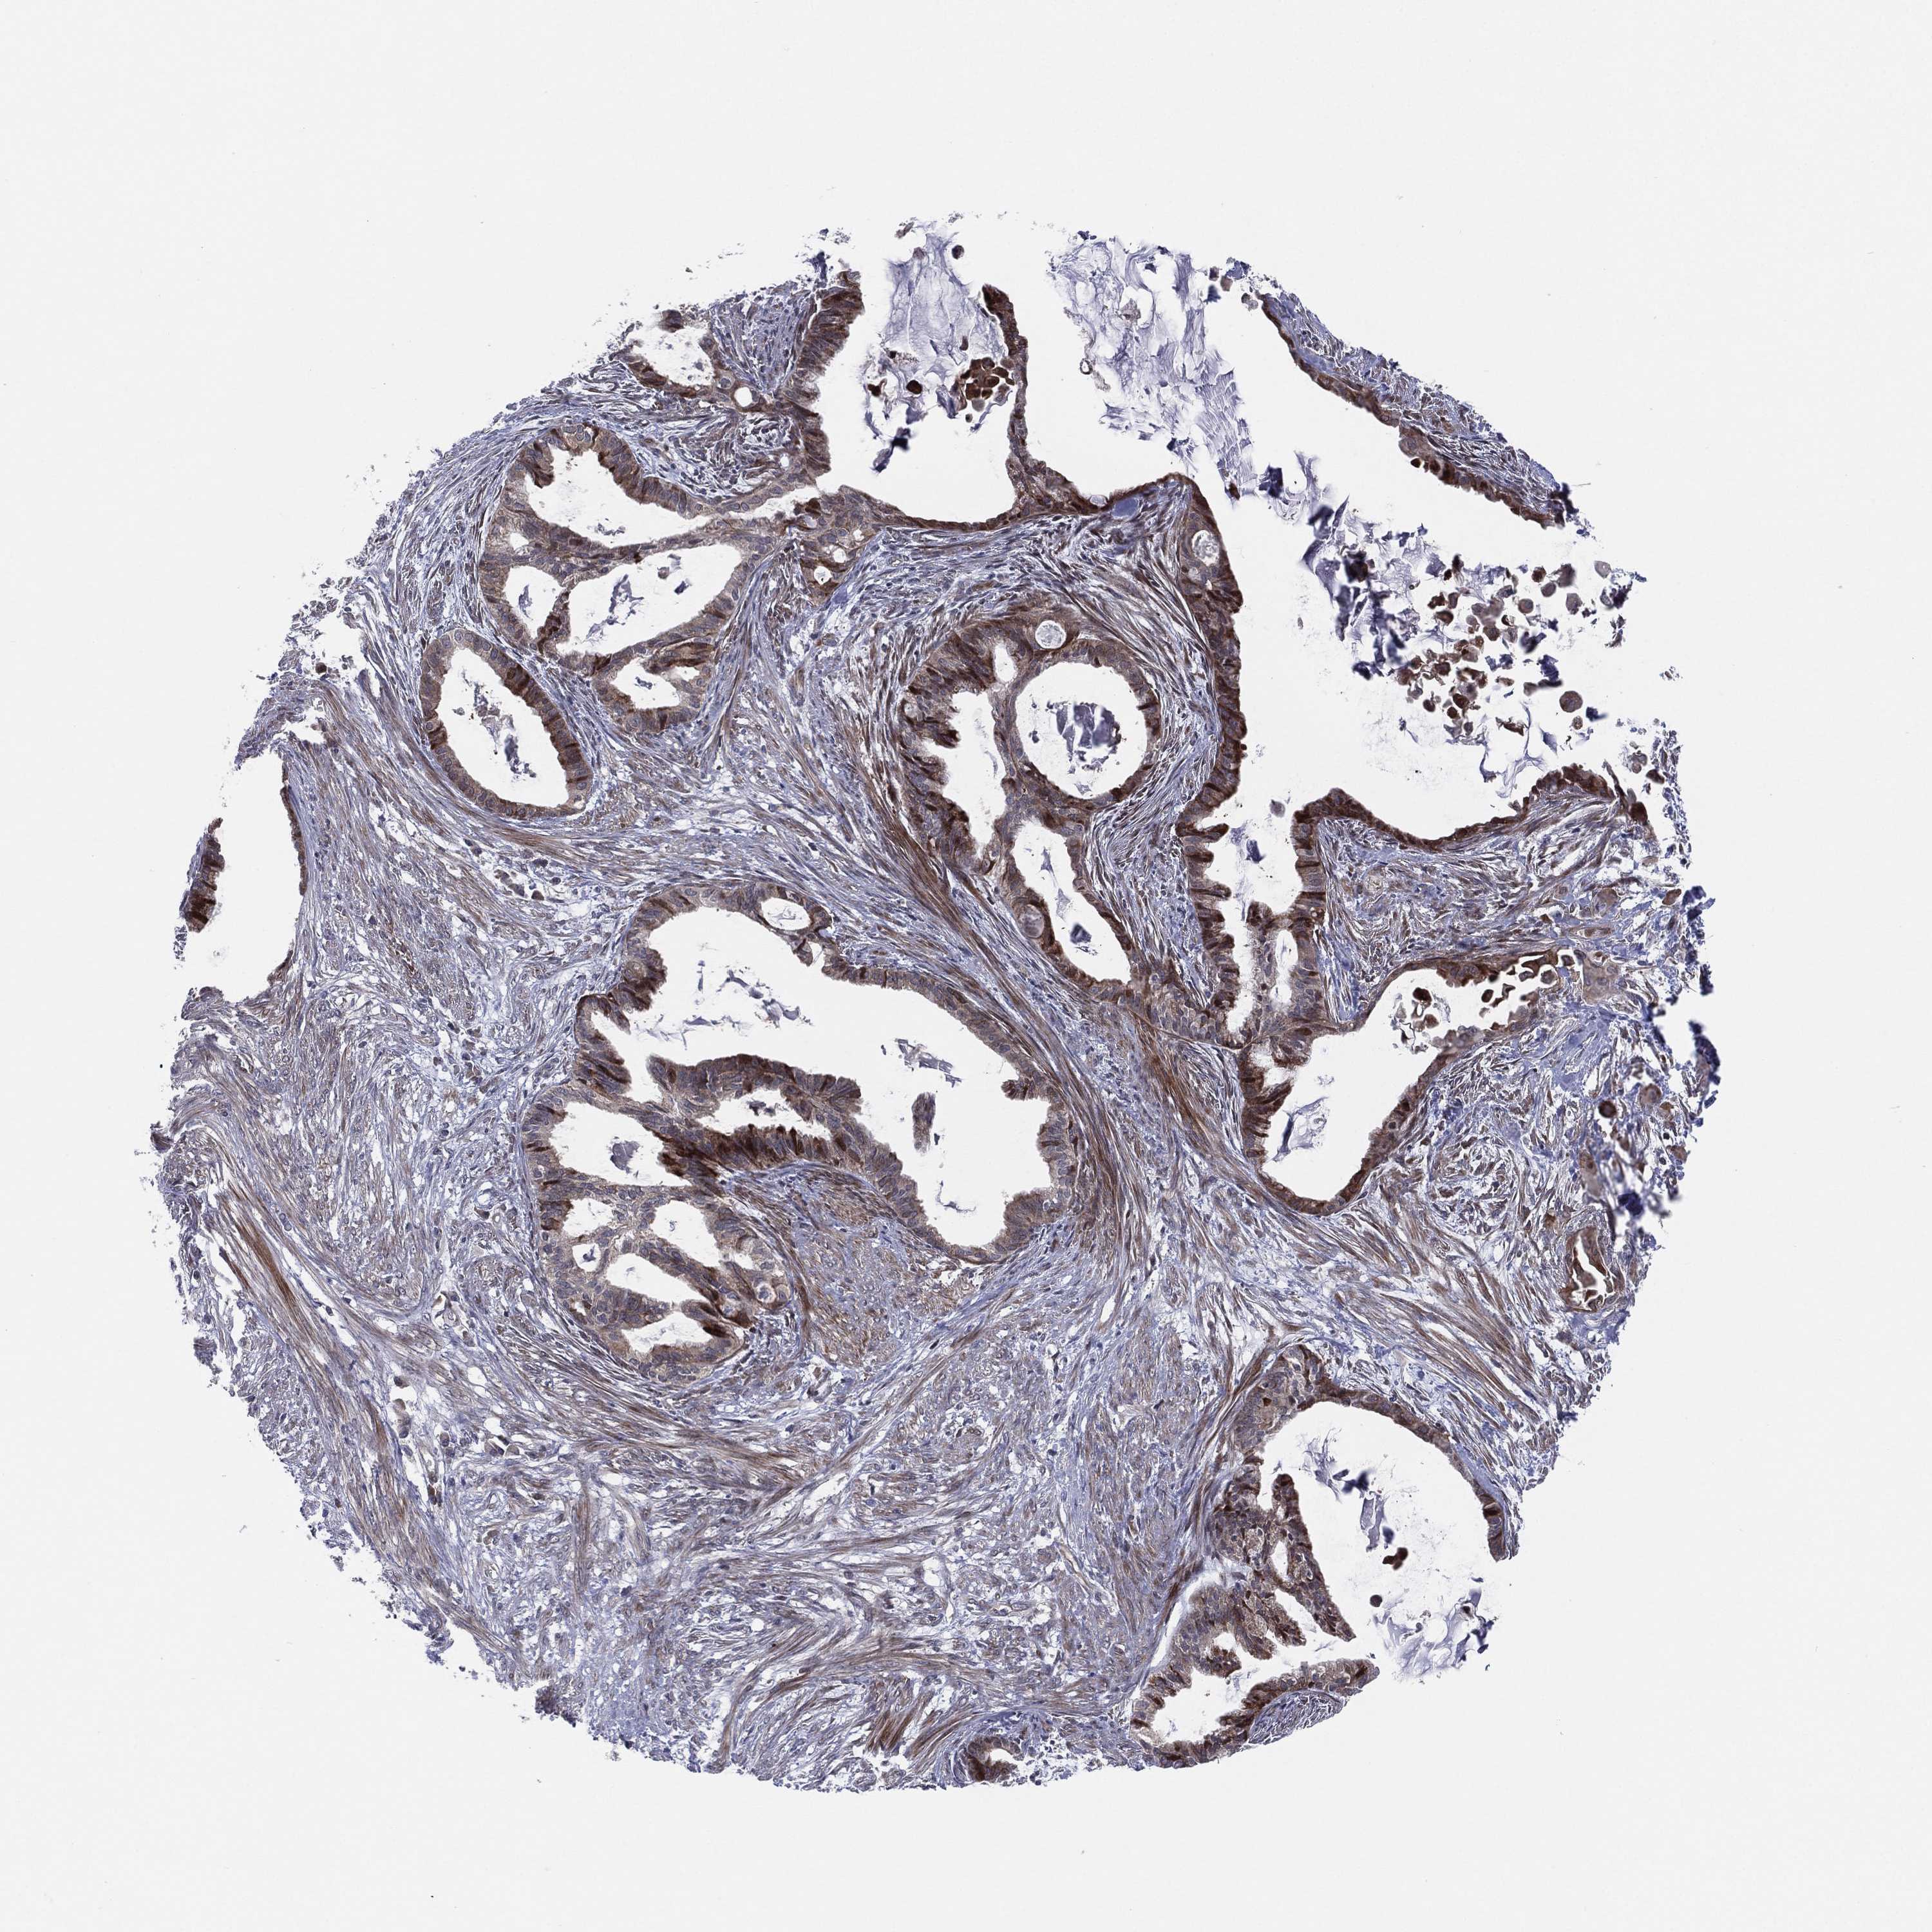

ENDOMETRIAL CANCER - Protein expressioni

A mouse-over function shows sample information and annotation data. Click on an image to view it in a full screen mode. Samples can be filtered based on level of antibody staining by selecting one or several of the following categories: high, medium, low and not detected. The assay and annotation is described here.

Note that samples used for immunohistochemistry by the Human Protein Atlas do not correspond to samples in the TCGA dataset.

Antibody stainingi

Antibody staining in the annotated cell types in the current human tissue is reported as not detected, low, medium, or high, based on conventional immunohistochemistry profiling in selected tissues. This score is based on the combination of the staining intensity and fraction of stained cells.

Each image is clickable and will lead to virtual microscopy that enables deeper exploration of all samples and also displays staining intensity scores, fraction scores and subcellular localization as well as patient and tissue information for each sample.

Antibody HPA047217

Antibody HPA054023

Antibody CAB079950

Staining

High

Medium

Low

Not detected

Intensity

Strong

Moderate

Weak

Negative

Quantity

>75%

75%-25%

<25%

None

Location

Nuclear

Cytoplasmic/membranous

Cytoplasmic/membranous,nuclear

Adenocarcinoma, NOS